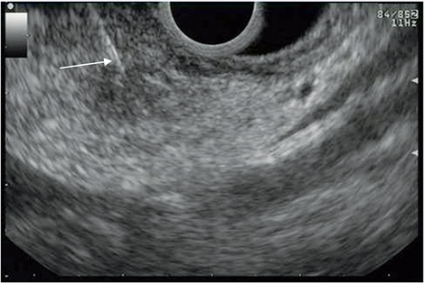

Submukösa processer är relativt ovanliga och orsakar sällan symtom. De upptäcks hos cirka 0,4 procent av patienter som genomgår rutinmässig gastroskopi. Ett vanligt problem med submukösa processer är att vanlig mukosabiopsi inte ger diagnostisk information. Endoskopiskt ultraljud är förstahandsmetod för att bedöma submukösa tumörer med avseende på storlek, vilket vägglager tumören utgår ifrån, ekogenitet och kanter samt för att differentiera mot extraintestinala inbuktningar. En av de viktigaste uppgifterna är att definiera vilket vägglager processen utgår ifrån (Figur 3).

Även om det ultraljudsmässiga utseendet är mycket användbart för att bedöma submukosala tumörer, finns det fall där finnålsaspiration eller vävnadsbiopsi kan vara avgörande för säker diagnos. En studie har visat att korrelationen mellan ultraljudsmässig bedömning och slutgiltig patologi är cirka 80 procent, och det diagnostiska utfallet av finnålsaspiration eller vävnadsbiopsi är mellan 80 och 90 procent [2, 3]. Endoskopiskt ultraljud kan ge vägledning för beslut om huruvida endoskopisk resektion är möjlig. Om förändringen engagerar muscularis propria eller djupare brukar man vanligtvis inte göra endoskopisk resektion på grund av risken för perforation.